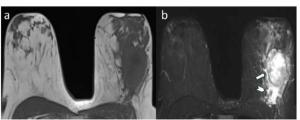

Breast MRI Study Links Peritumoral Edema to Reduced Disease-Free Survival from Breast Cancer in Young Women